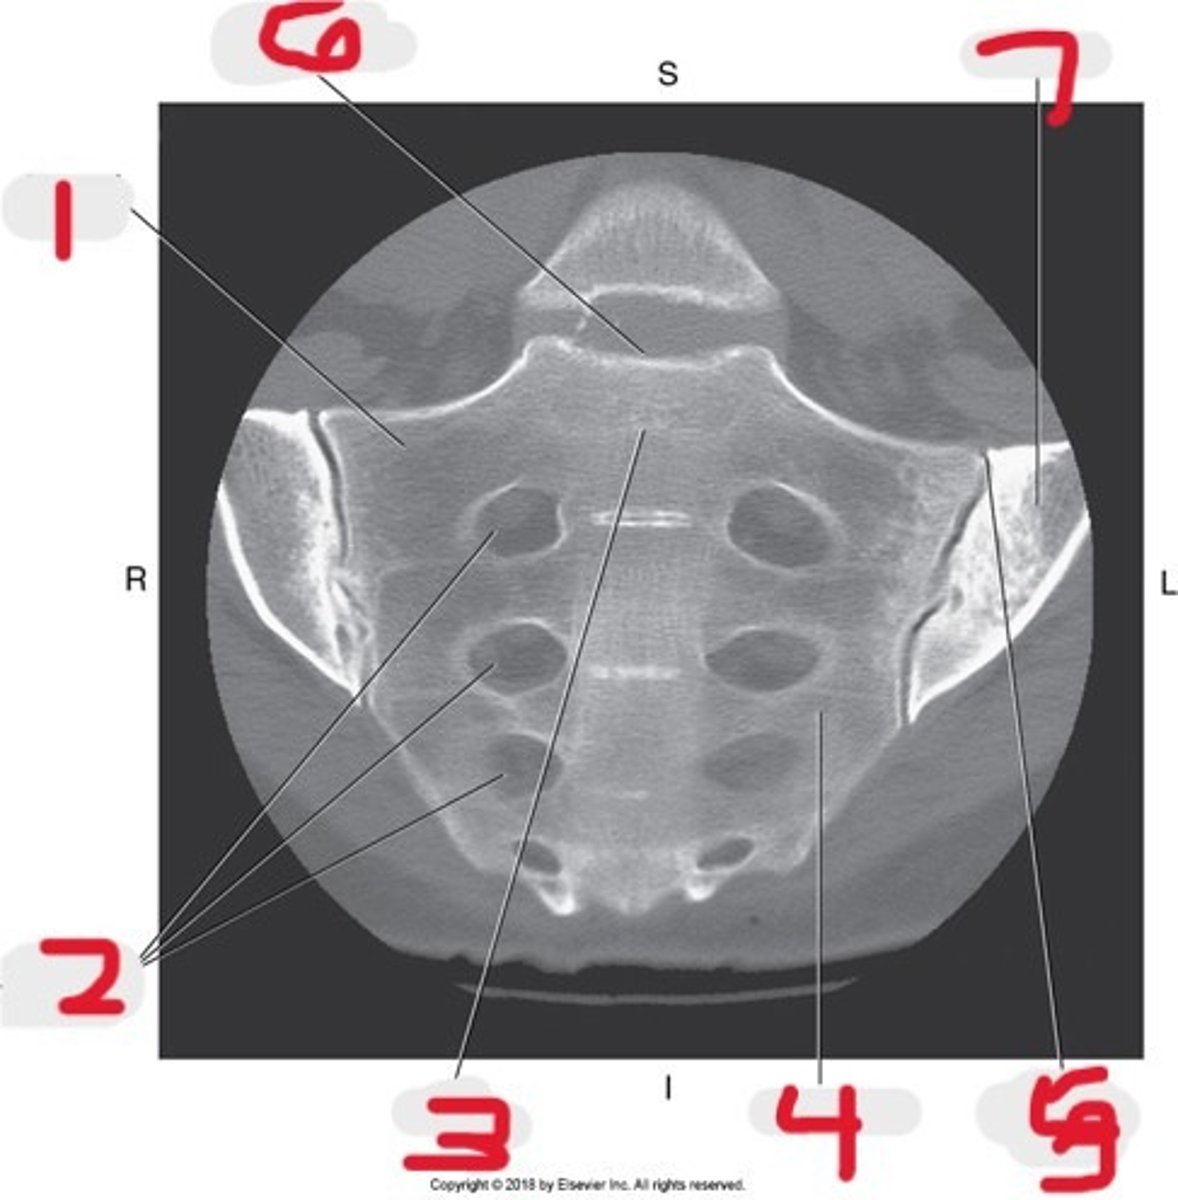

1) Lateral mass

2) Sacral foramina

3) Body

4) Sacrum

5) SI joint

6) Sacral promontory

7) Ilium

Name all numbered structures

1) SI joint

2) Body

3) Sacral promontory

4) Sacral canal

5) Ilium

6) Lateral mass

7) Articular process

Name all numbered structures